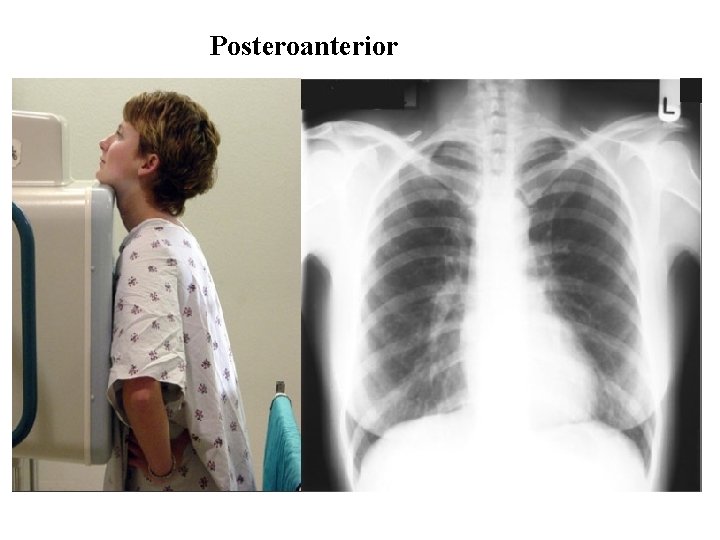

Radiography • Different views of the chest can be obtained by changing the orientation of the body and the direction of the x-ray beams. • The most common views are: ØPosteroanterior(PA), ØAnteroposterior (AP), ØLateral.

Posteroanterior